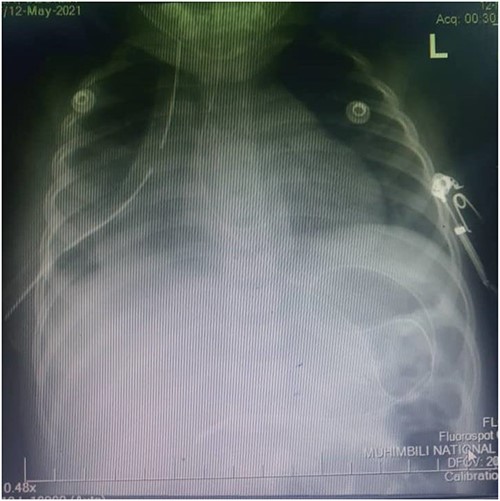

Figure 4 shows a control plain chest radiography taken after the right hemidiaphragmatic repair, it describing adequate right lung volume of expansion, with normal hemidiaphragmatic dome and obvious cardiac silhouette.